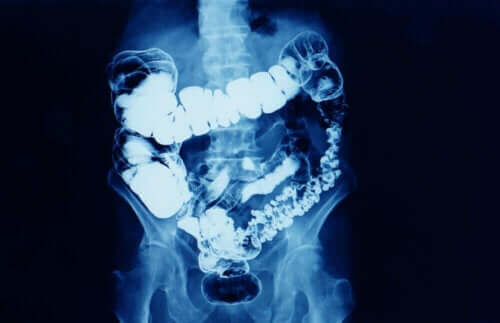

الجليسرول هو المادة الفعالة في تحاميل الجليسرين. هذه المادة لها تأثير ملين عندما يتم استعمالها مستقيميًا (عن طريق فتحة الشرج). هذا التأثير يرجع إلى تليين المادة للبراز وإنتاجها لتهيج موضعي خفيف يتسبب في تحفيز حركة التمعج المعوي.

- تهييج موضعي للغشاء المخاطي للمستقيم: هذا التأثير لا يمس جدران الأمعاء. وهو يتسبب في انقباض المستقيم، مما يحفز عملية إخراج البراز.

- التأثير التناضحي: الجليسرول يمتص الماء، وبجانب خصائصه المشحمة، يؤدي ذلك إلى تليين البراز وتسهيل إخراجه.